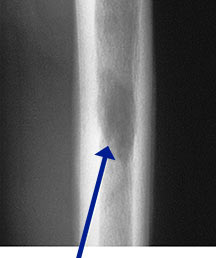

- May arise from any bone and any site within a bone (epiphyseal, metaphyseal, diaphyseal)

- Radiographically variable appearance: may appear benign (geographic) or malignant (permeative or moth eaten)

Sites:

- Flat Bones (most common—70%)

- Humerus